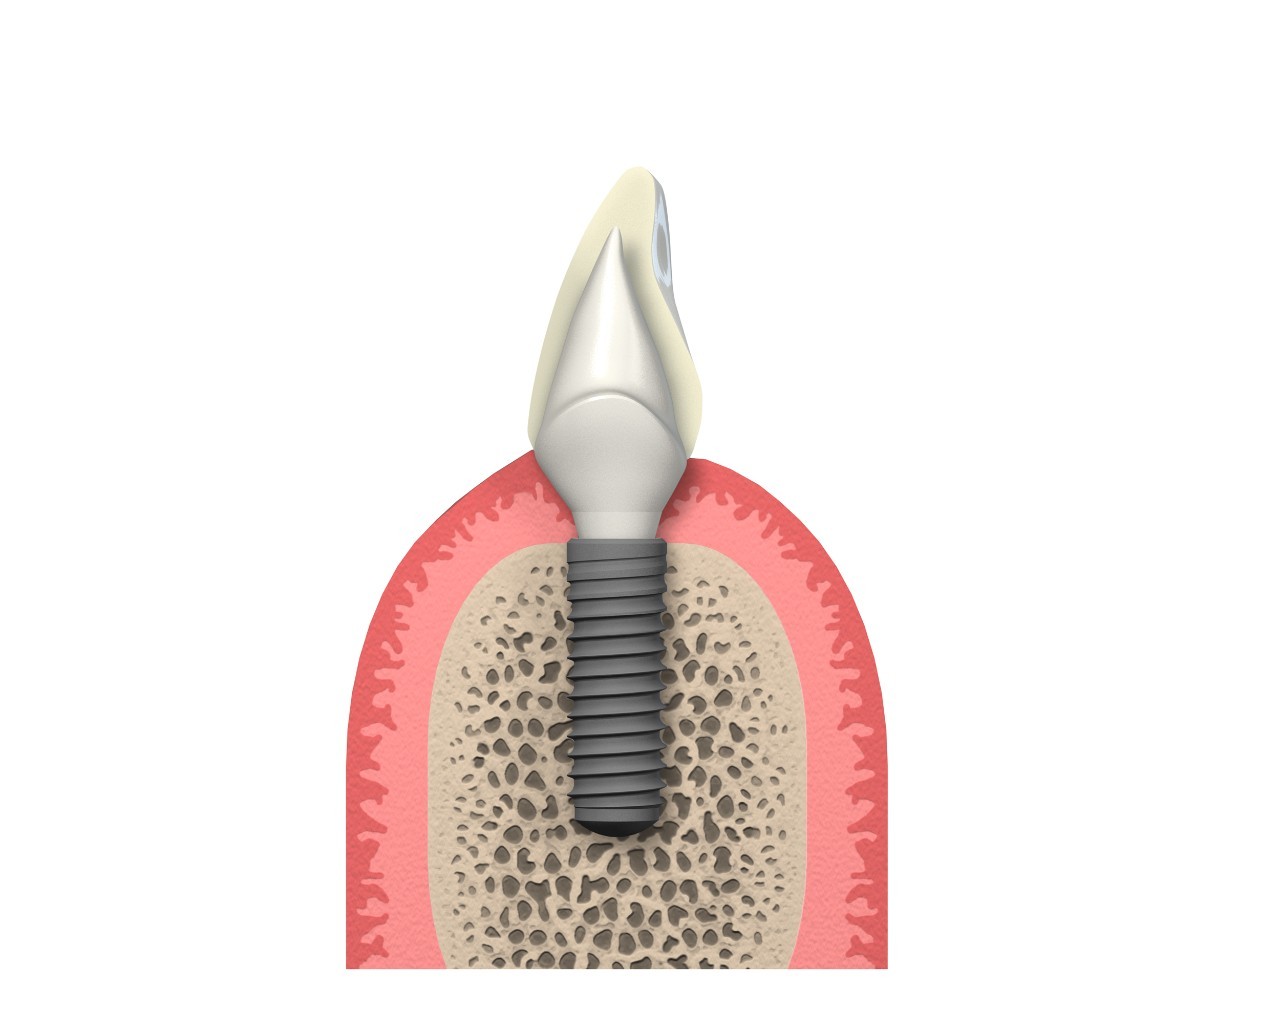

¿Qué es un implante?

Los implantes dentales son dispositivos que, insertados en el hueso, funcionan o actúan como una raíz artificial, soportando así la futura corona protética por medio de un aditamento intermedio conocido como pilar.

Es importante diferenciar entre cantidad y calidad de hueso. De la cantidad ósea dependerá el tipo de implante que se vaya a colocar, en términos de diámetro y longitud. Por su parte, la calidad ósea se perfila como factor clave al que estará supeditado la estabilidad de los implantes. La realización de un TAC (Tomografía Axial Computarizada) se presenta como el método radiodiagnóstico más fiable para la evaluación de los parámetros anteriormente descritos y llevar así una adecuada planificación de cada caso.

Consideraciones tras la colocación de los implantes

El concepto de osteointegración u oseointegración se define como la conexión directa, estructural y funcional entre el hueso y la superficie del implante durante las cargas funcionales o masticatorias. Este fenómeno dependerá de la capacidad de cicatrización, reparación y remodelado de los tejidos, tanto del hueso como de la encía. Así, para poder establecer un pronóstico predecible, la manipulación y cuidado meticulosos de los mismos resulta clave para poder hablar de éxito clínico.

Los implantes como medio para una prótesis

Una vez respetado el período de cicatrización, se llevará a cabo la restauración protética, esto es, conectar el implante osteointegrado a una corona a través de un elemento intermedio conocido como pilar. Este procedimiento puede realizarse de manera atornillada o cementada.